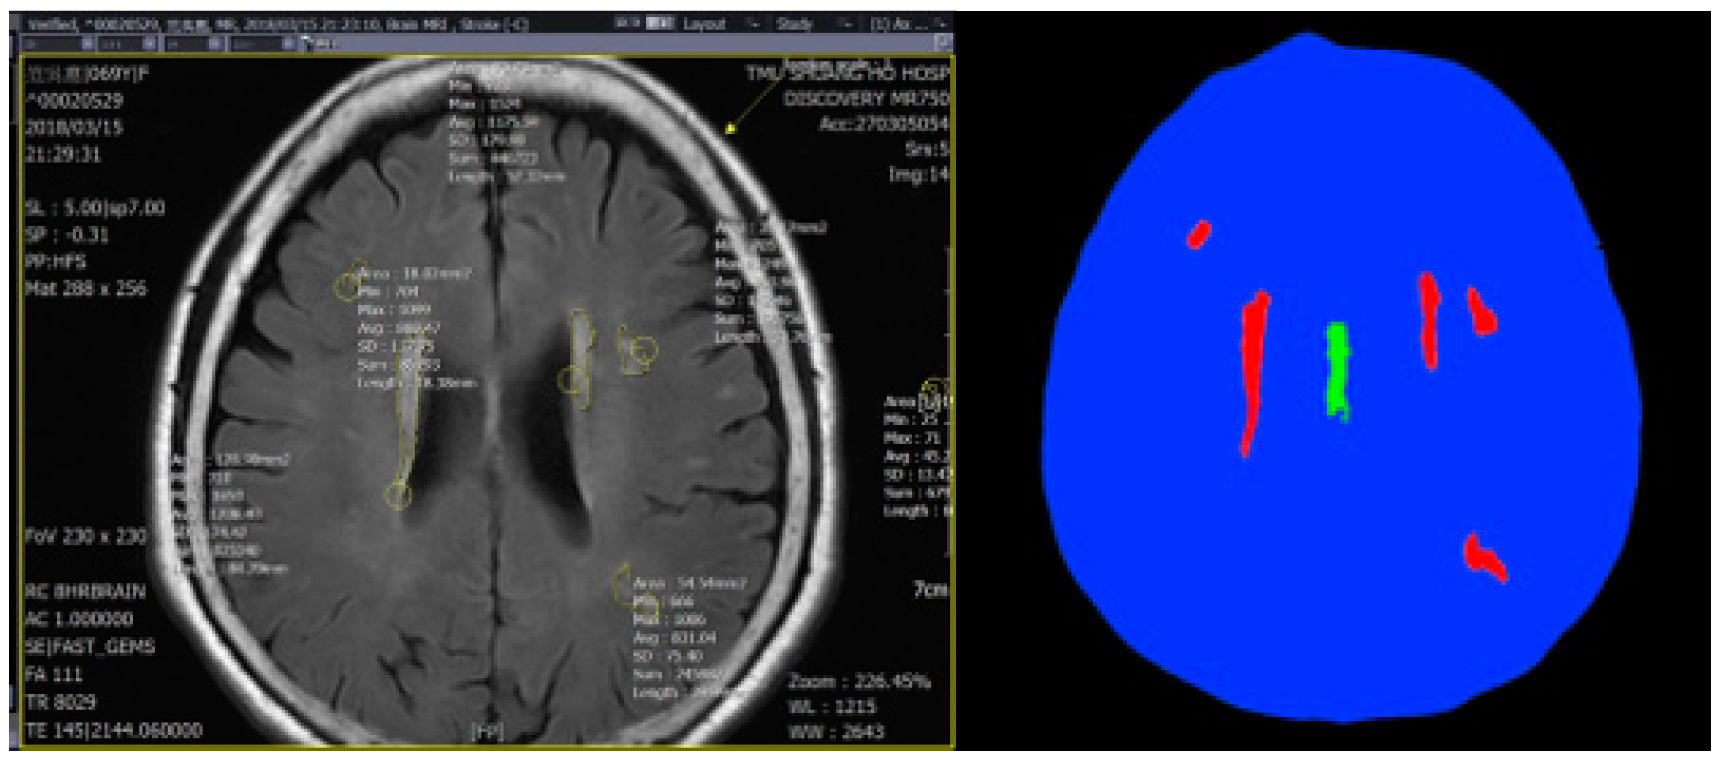

3.1. Data Preprocessing

3.2. Training Model

4. Experiment Results